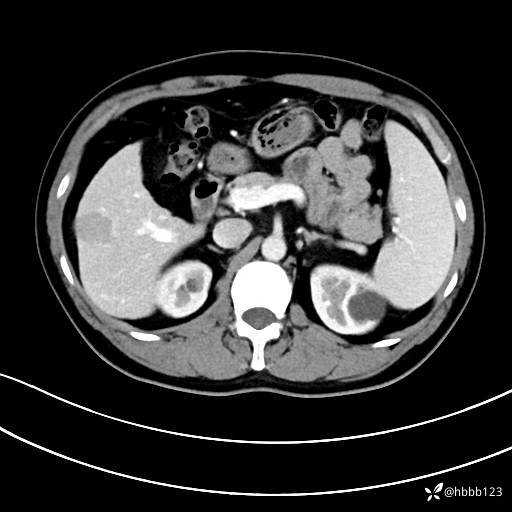

门诊完善上腹部CT平扫+增强。

延迟期:

典型的”****“特征!你能秒杀吗?